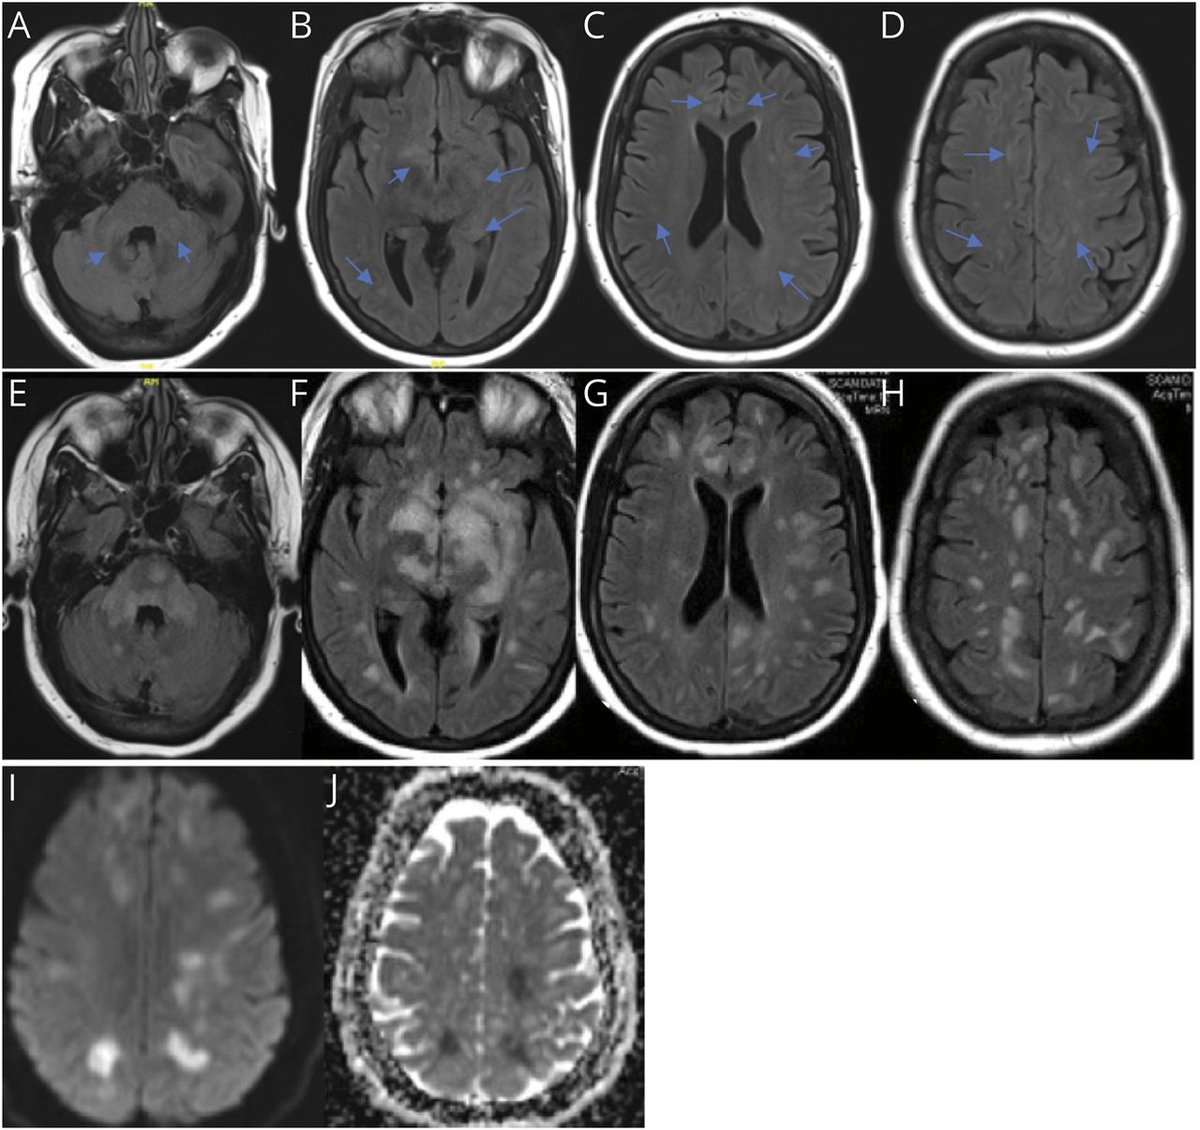

We have found that patients with neurologic manifestations of #COVID19 have inflammatory cytokines in their CSF, at levels approaching that of CAR T cell neurotoxicity. What’s more, this can be detected weeks after the acute infection. Role for steroids? mskcc.org/news/msk-resea…